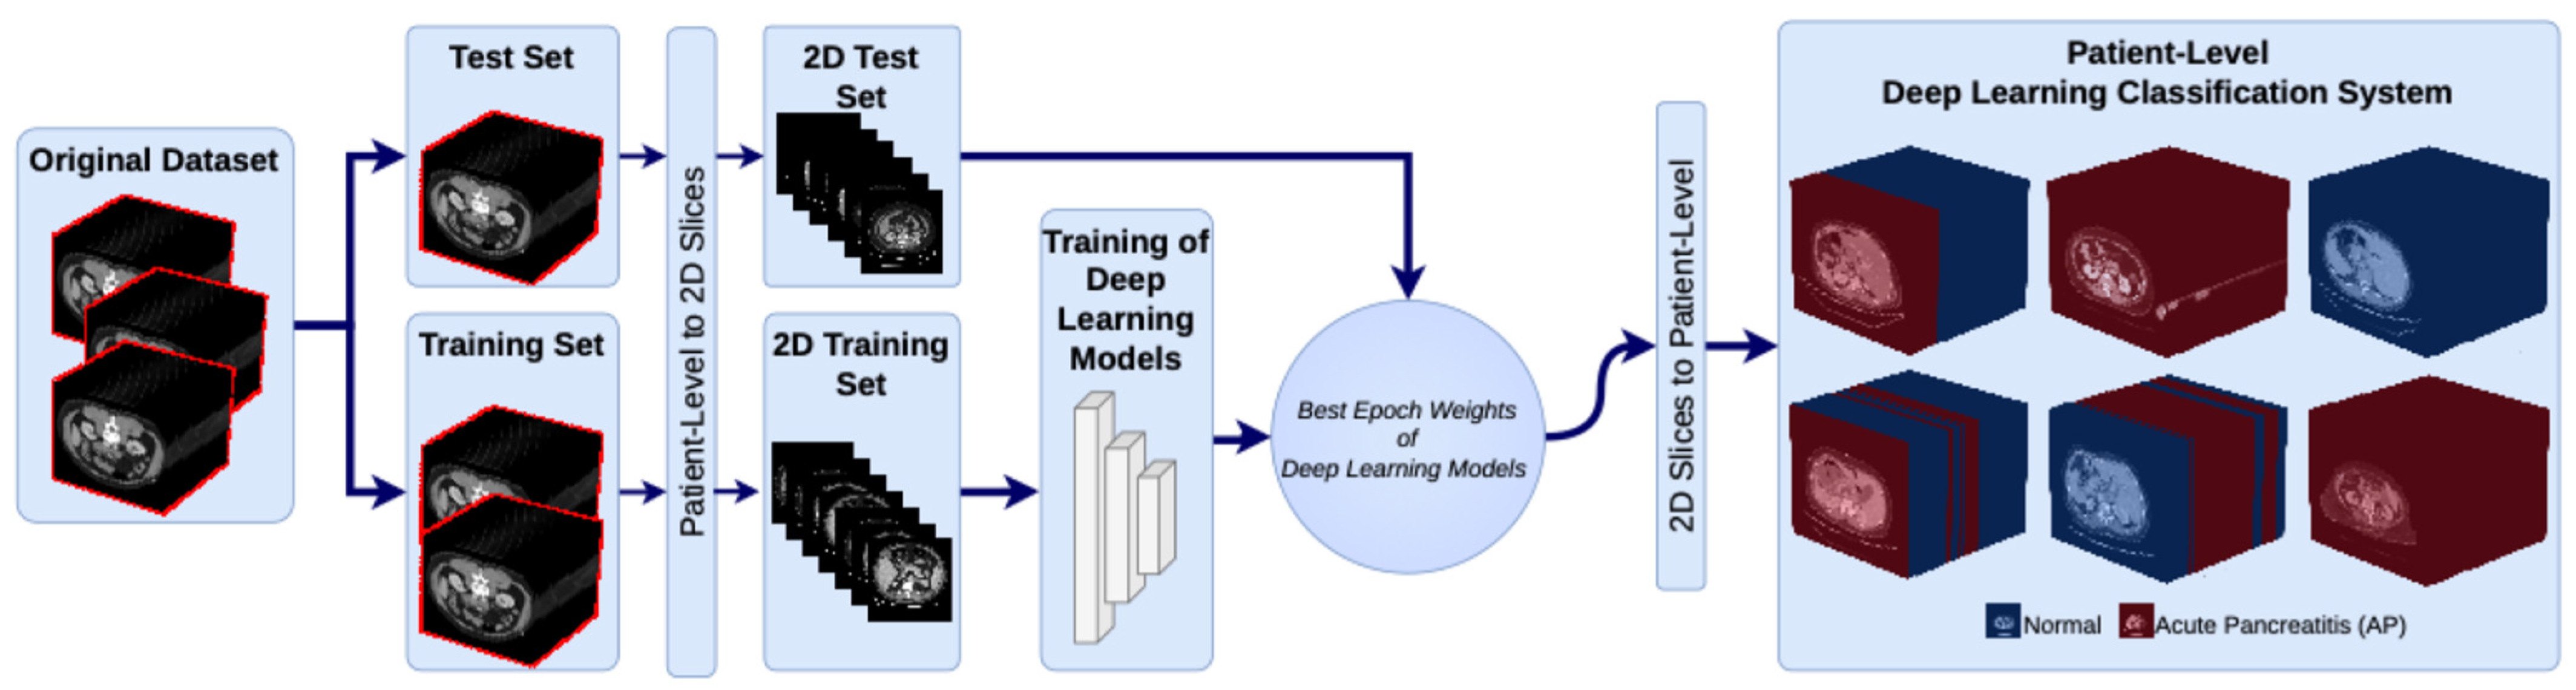

The pancreatic dataset, which was created specifically for this study, was generated from CT images of patients with AP and normal pancreatic tissue. The dataset contains CT images from 183 patients, 103 of whom are in the normal group and 80 of whom are in the AP group. At the beginning of the data preparation process, the patients were divided into two classes according to their clinical diagnoses: normal and AP. The appearance of pancreatic tissue can be influenced by CT acquisition protocols and contrast enhancement phases, not only due to pathology, but also due to imaging conditions. In our dataset, CT scans were acquired under routine clinical conditions. Therefore, images obtained using different contrast enhancement phases may be included in both normal and AP cases. The image windowing parameters were set to a window width (WW) of 400 and a window level (WL) of 50 to ensure optimal contrast and visibility of the pancreatic tissue. These settings allow for more distinct visualization of the pancreatic parenchyma and surrounding anatomical structures, highlighting the model’s features. To prevent slice-level from the same patient from appearing in both the training and test sets and to reliably evaluate the model’s generalization ability, the dataset was split into training and test sets on a patient-by-patient basis. To avoid analyzing anatomical regions that could affect classification performance, only slices with clearly visible pancreatic tissue were selected for the analysis.

Each patient’s CT scan consists of 200 to 450 axial slices. To train deep learning models, all CT slices were converted from the original DICOM format to PNG format. In patient-level, approximately 80% of the data was allocated to the training set, and the remaining 20% was allocated to the test set. Of the patients in the normal group, 82 were in the training set and 21 were in the test set. Of the patients in the AP group, 64 were in the training set and 16 were in the test set. This distribution provides a balanced training and testing structure for both groups. When evaluated on a slice-level basis, 4929 out of 6225 (79.18%) slices in the normal group were in the training set, and 1296 out of 6225 (20.82%) were in the test set. In the AP group, out of 5542 slices, 4309 (77.75%) were in the training set, and 1233 (22.25%) were in the test set. In addition, the model training did not include demographic data or laboratory findings.

During the training process, the deep learning models were trained using only the training set. The weighting parameters that provided the best performance for each model were then determined. Afterwards, a test dataset was used to evaluate the performance of the models with these optimal weights. Model performance was analyzed at two levels. First, we evaluated slice-level classification performance, followed by patient-level classification performance, the latter of which is more suitable for clinical applications. In this study, patient-level classification was performed using an outcome-level aggregation strategy rather than a feature-level one. Specifically, the model independently classified each CT slice, and the final patient-level decision was obtained by aggregating the predictions of all slices belonging to the same patient. The aggregation was performed using a majority voting approach, whereby the final class label was determined based on the most common prediction across all slices. This approach reduces the impact of potential misclassifications at slice level and provides a more stable, clinically meaningful prediction at patient level.